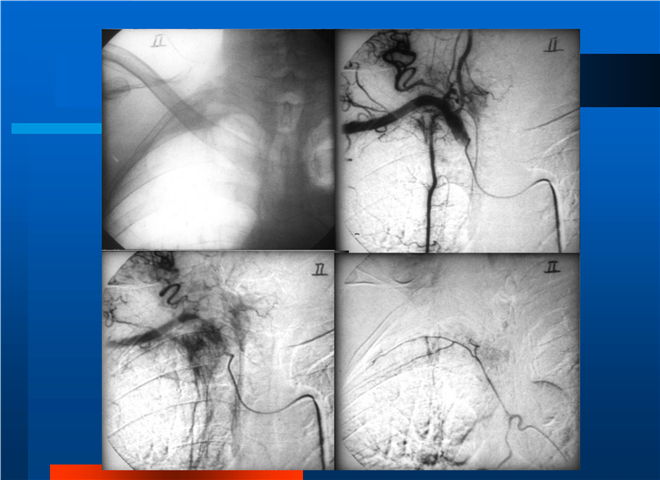

04_肺癌的介入治疗